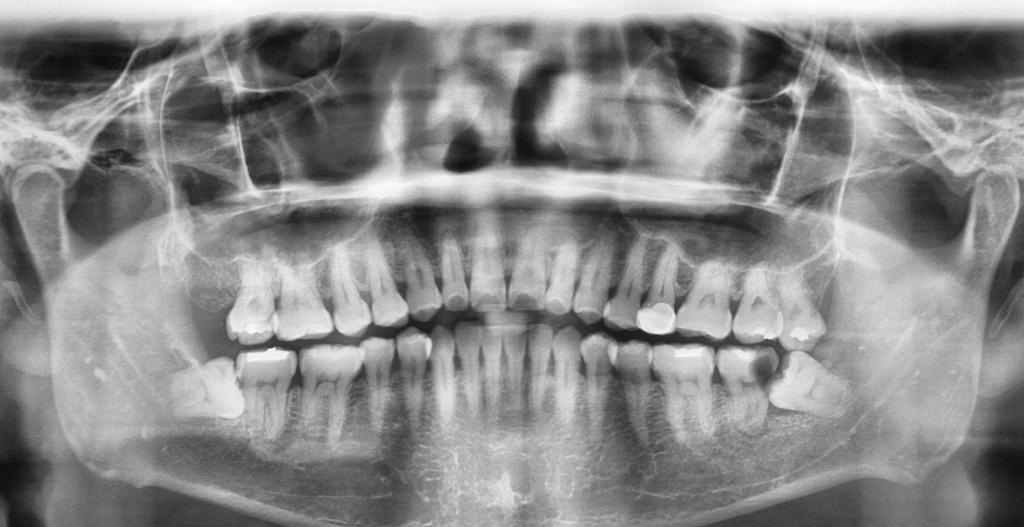

Tooth loss can be due to decay trauma and even gum disease . Tooth loss can affect appearance and function and have an impact on quality of life .

There are different methods for replace missing teeth and each options have their advantages and disadvantages

However , for an implant to work it requires sufficient bone

– Require sufficient bone